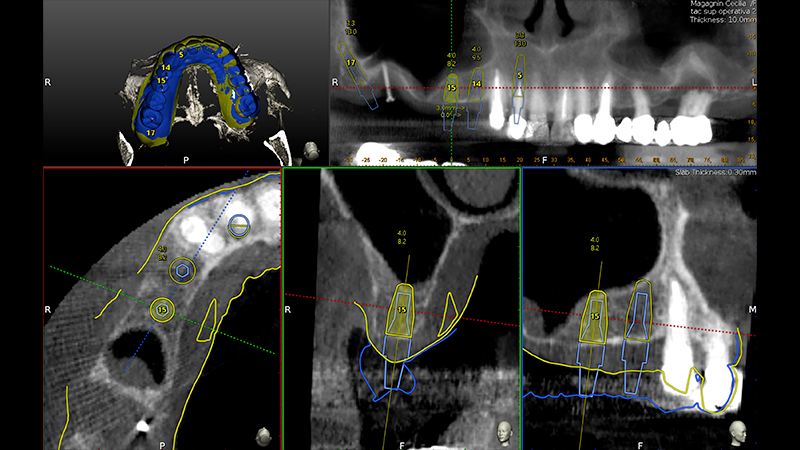

Una volta atteso 3 mesi di guarigione dei tessuti molli, si procedeva all'esecuzione della TAC mediante repere codificato secondo il protocollo "impression registration" e al posizionamento di una minivite Ustomed in zona 16 per aumentare la precisione del navigatore nella lunga sella edentula distale (Figs. 5, 6, 7, 8).

Guarigione dopo 3 mesi, inserimento minivite Ustomed per inserire repere ed aumentare la precisione del Navigatore in zona edentula. Esecuzione della Cone Beam con repere per il protocollo "instant registration"

Fig. 5 - Guarigione dopo 3 mesi, inserimento minivite Ustomed per inserire repere ed aumentare la precisione del Navigatore in zona edentula. Esecuzione della Cone Beam con repere per il protocollo "instant registration"

esecuzione Cone Beam

Fig. 6 - Guarigione dopo 3 mesi, inserimento minivite Ustomed per inserire repere ed aumentare la precisione del Navigatore in zona edentula. Esecuzione della Cone Beam con repere per il protocollo "instant registration"

Veniva eseguita la pianificazione del caso con l'utilizzo dell'STL della Biocopia (Fig. 9) e della gengiva guarita (Fig. 10), e di tutti gli impianti: zona 12 con pianificazione post-estrattiva flapless con Socket Shield (Fig. 11), zona 14 (Fig. 12), zona 15 (Fig. 13) e zona pterigoidea (Fig. 14). Dopo la chirurgia (Video 1 e 2), OPT post-operatoria e endorali venivano fatte per valutare il rialzo di seno trans-crestale (Figs. 15, 16, 17, 18).

Pianificazione chirurgica della posizione implantare

Fig. 9 - Pianificazione chirurgica della posizione implantare su Software Navident (Claronav) basandosi sulla posizione dei denti originali mediante sovrapposizione di impronta ottica con e senza i denti (STL). Particolare attenzione è stata posta al parallelismo degli impianti 15 e 14, al corretto posizionamento con tecnica Socket Shield su 12 e alla correzione predefinita di 30° del moncone dell'impianto pterigoideo per mantenere il parallelismo conometrico protesico

Pianificazione chirurgica della posizione implantare su Software Navident

Fig. 10 - Pianificazione chirurgica della posizione implantare su Software Navident (Claronav) basandosi sulla posizione dei denti originali mediante sovrapposizione di impronta ottica con e senza i denti (STL). Particolare attenzione è stata posta al parallelismo degli impianti 15 e 14, al corretto posizionamento con tecnica Socket Shield su 12 e alla correzione predefinita di 30° del moncone dell'impianto pterigoideo per mantenere il parallelismo conometrico protesico

Fig. 13 - Pianificazione chirurgica della posizione implantare su Software Navident (Claronav) basandosi sulla posizione dei denti originali mediante sovrapposizione di impronta ottica con e senza i denti (STL). Particolare attenzione è stata posta al parallelismo degli impianti 15 e 14, al corretto posizionamento con tecnica Socket Shield su 12 e alla correzione predefinita di 30° del moncone dell'impianto pterigoideo per mantenere il parallelismo conometrico protesico